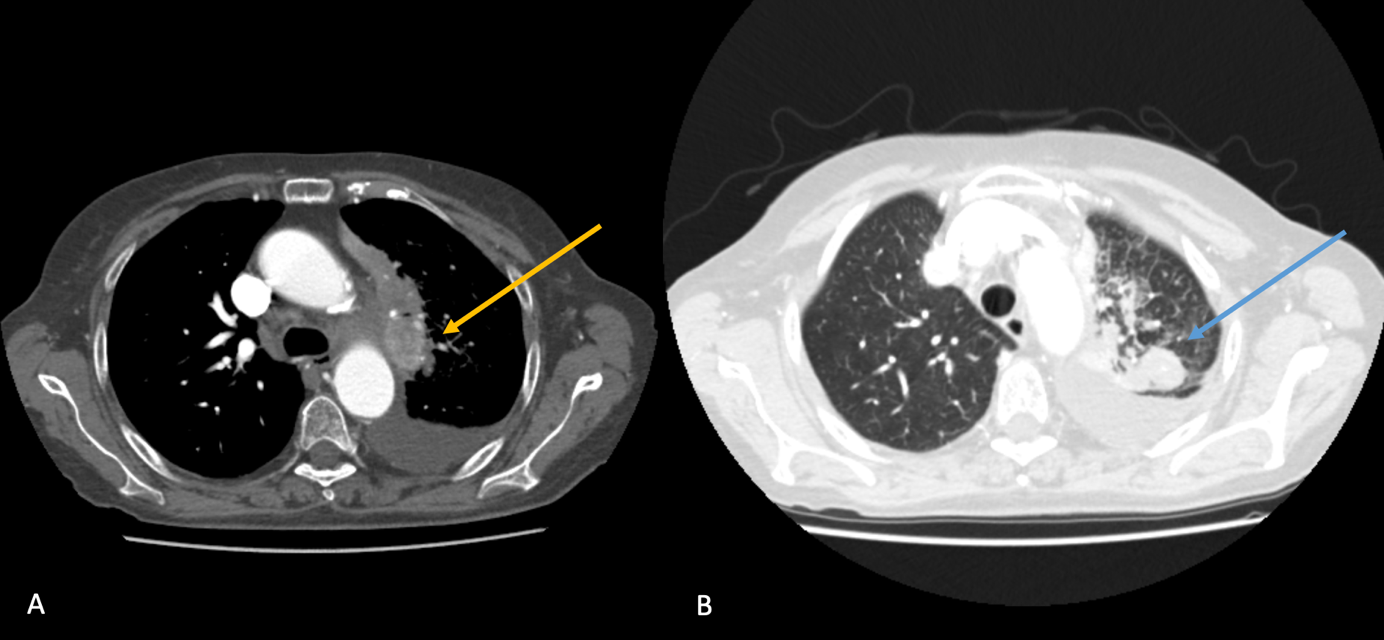

A, B, C. Axial und koronal rekonstruierte CT-Untersuchung in venöser Kontrastierung, hier zeigen sich zwei Rundherde im linken Oberlappen, Zeichnungsvermehrung mit retikulo-nodulärem Verteilungsmuster sowie ein moderater Pleuraerguss linksseitig.

D. T2 TSE koronal dark-fluid Sequenz, hier zeigt sich eine deutliche Inflammation des intrakonalen, retrobulbären Fettgewebes linksseitig.

E. Axiale T1 MPRAGE Post-KM, hier zeigt sich eine deutliche Verdickung und Enhancement der linksseitigen Pachymeningen.